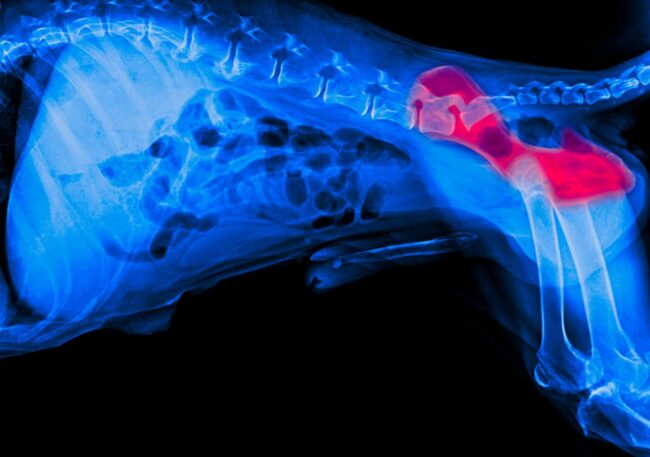

Dysplazja stawów u psa: Objawy, leczenie i rola odpowiedniej diety

Czy zauważyłeś, że Twój pies unika dłuższych spacerów, kuleje po wysiłku lub z trudem wstaje po odpoczynku? To mogą być pierwsze oznaki dysplazji stawów – choroby, która dotyka psy różnych ras i w różnym wieku. Dysplazja to schorzenie, które może znacząco obniżyć komfort życia psa, ale dobra wiadomość jest taka, że odpowiednie leczenie, dieta i…